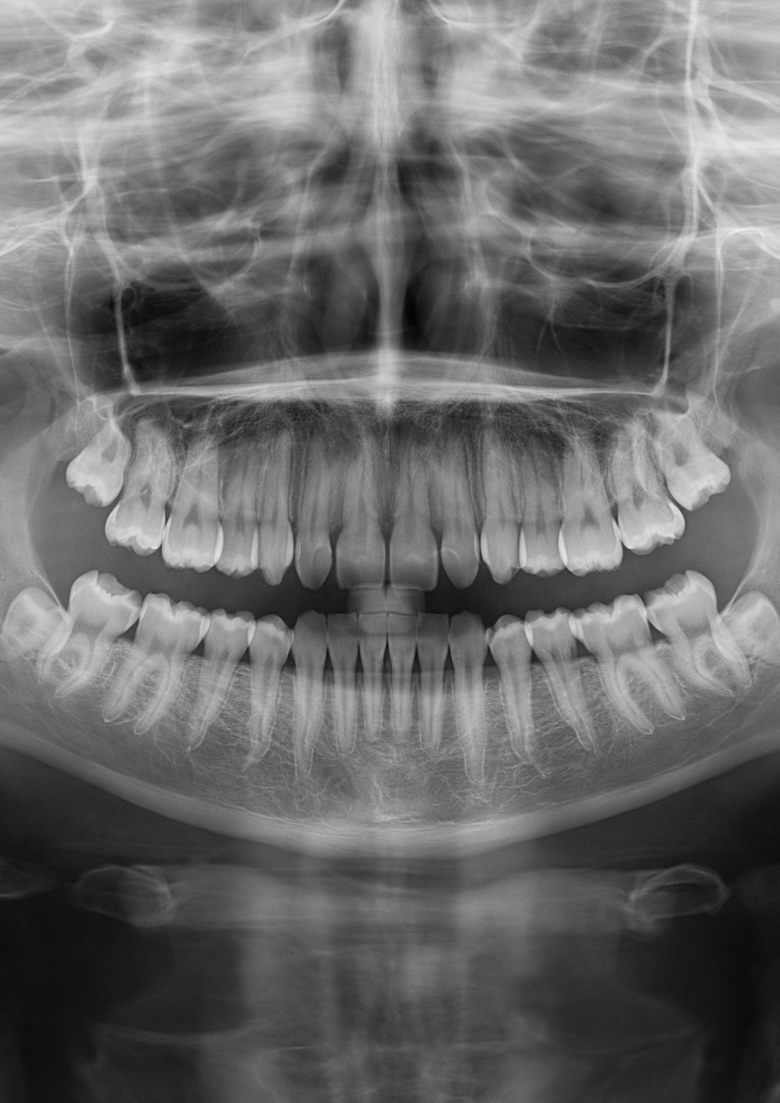

La Cone-beam è una tecnica di imaging, nello specifico una tomografia computerizzata che, attraverso dei raggi X emessi a forma di cono, permette di acquisire delle immagini nelle 3 dimensioni spaziali della sezione anatomica di interesse. Grazie al rendimento tridimensionale è possibile avere una visione estremamente dettagliata della zona da analizzare e così intervenire con precisione. Viene utilizzata prevalentemente in fase pre-operatoria in chirurgia orale per acquisire tutte le informazioni necessarie precedentemente all’operazione e poter delineare in anticipo le modalità di intervento, diminuendo enormemente il rischio di ledere strutture vicine durante le manovre.

Con la Cone-beam si sono superate notevolmente le metodiche di TC tradizionale, in quanto questa tecnica è inserita la terza dimensione e le radiazioni a cui è sottoposto il paziente sono state ridotte di circa 6 volte. Inoltre è completamente indolore. Anche la durata dell’esame è molto breve: necessita di circa 30-40 secondi, in cui il paziente può accomodarsi comodamente seduto oppure rimanere anche in piedi.